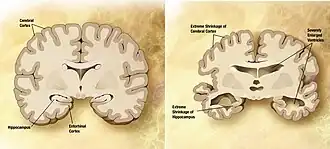

Epigenetic dysregulation and neurological disorders

Epigenetic dysregulation, or alterations in epigenomic machinery, can cause DNA methylation and histone acetylation processes to go rogue. The epigenetic machinery influences neural differentiation regulation (i.e. neurogenesis)[36] and are also involved in processes related to memory consolidation and learning in healthy individuals.[37] DNA methylation and histone modifications play a critical role in modulating gene expression related to synaptic plasticity, which is essential for learning and memory formation.[32] Increasing age can produce various epigenetic changes such as reduced global heterochromatin, nucleosome remodeling, altered histone marks, and changes in DNA methylation. For instance, nucleosome loss occurs due to aging because core histone proteins are lost and less protein synthesis occurs.[38] Epigenetic control of enhancer regions in neurons has been linked to neurodegenerative diseases, particularly Alzheimer's disease, where dysregulated chromatin accessibility contributes to neuronal dysfunction.[39] Notably, chromatin loops that regulate enhancer-promoter interactions appear to be disrupted in neurodegenerative conditions, leading to widespread transcriptional alterations. As aging is the main risk for many neurological disorders, epigenetic dysregulation can in turn lead to alterations on the transcriptional level of genes involved in the pathogenesis of neural degenerative diseases such as Parkinson's disease, Alzheimer's disease, Huntington's disease, schizophrenia, and bipolar disease.[1][40]

Alzheimer's disease

MicroRNA expression is critical for neurogenesis. In patients with Alzheimer's disease miR-9 and miR-128 is upregulated, while miR-15a is downregulated.[41] These microRNAs have been shown to regulate key neuronal genes involved in synaptic plasticity and neuroinflammation, further linking their dysregulation to cognitive decline in Alzheimer's patients.[32] Alzheimer's patients also show decreases in brain-derived neurotrophic factor, which has been shown to be repressed through DNA methylation.[16] BDNF reduction impairs neuronal survival and synaptic function, exacerbating memory deficits associated with the disease.[32] Loss of BDNF signaling is associated with synaptic atrophy, contributing to the hallmark cognitive deficits of Alzheimer's disease. Although one of the strongest pieces of evidence for epigenetic influence in Alzheimer's is the gene that controls the protein responsible for amyloid plaque formation, APP. This gene has very high GC content in its promoter region, meaning that it is highly susceptible to DNA methylation. This promoter site has been shown to naturally reduce methylation with aging, exemplifying the parallels between aging and Alzheimer's already well known.[42][43] Epigenetic regulation of enhancer regions in neurons has also been implicated in Alzheimer's disease, with studies showing that chromatin accessibility changes contribute to disease progression by altering transcriptional programs essential for neuronal function. Additionally, recent findings suggest that differential DNA methylation of tau-related genes contributes to tau pathology, another defining feature of Alzheimer's disease.

DNA methylation's age relation has been further investigated in the promoter regions of several Alzheimer's related genes in the brains of postmortem late-onset Alzheimer's disease patients. The older patients seem to have more abnormal epigenetic machinery than the younger patients, despite the fact that both had died from Alzheimer's. Though this in of itself is not conclusive evidence of anything, it has led to an age-related epigenetic drift theory where abnormalities in epigenetic machinery and exposure to certain environmental factors which occur earlier in life lead to aberrant DNA methylation patterns far later, contributing to sporadic Alzheimer's Disease predisposition.[43] This epigenetic drift theory suggests that cumulative changes in DNA methylation, histone modifications, and chromatin remodeling over time contribute to neurodegeneration, providing a potential link between aging and late-onset Alzheimer's disease.[34]

Histone modifications may also have an impact in Alzheimer's disease, but the differences between HDAC effects in rodent brains compared to human brains have researchers puzzled.[43] As the focus for neurodegenerative diseases begins to shift towards epigenetic pharmacology, it can be expected that the interactions of histone modifications with respect to neurogenesis will become more clear. Histone deacetylase (HDAC) inhibitors have shown promise in preclinical studies, as they can restore cognitive function by enhancing synaptic plasticity and memory consolidation, though their effects in humans remain under investigation.[34]